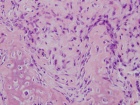

Patient is an 18 y/o female who presented c/o four month hx. of L. knee pain and swelling; she attended PT and x-rays revealed a lesion

PMH: unremarkable; PE: L. distal thigh w/ palpable warm mass; full PROM; NVI

Zoom image: Cell stain Cell stain.